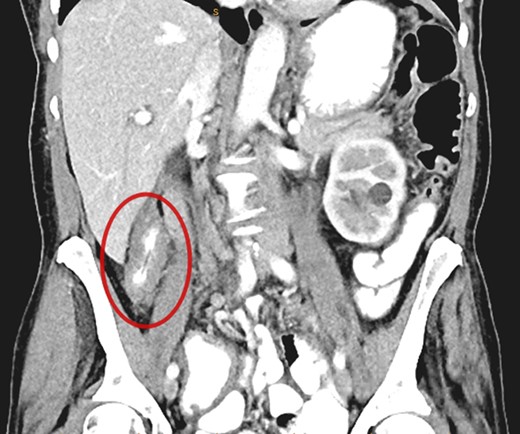

A CT abdomen/pelvis performed on the same day demonstrated contiguous bowel wall thickening from terminal ileum extending to distal ascending colon. There was no evidence of disease elsewhere; notably, there was no evidence of peritoneal disease or ascites.

Submucosal biopsies from ascending colon unexpectedly demonstrated metastatic carcinoma consistent with female genital tract origin—CK7 positive; CK20 negative; PAX-8/WT-1/ER/CA125 all positive. A PET/CT was performed on the basis of the histological findings, which demonstrated intense FDG-avidity in the known site of disease in the ascending colon (Figs 2 and 3), as well as a separate focus of increased metabolism in the left pelvic side-wall (Fig. 4), which was presumed to represent an ovarian primary. There was no evidence of nodal or peritoneal disease, however, note was made of mild bilateral hydroureter without clear transition point. CA125 was 118 U/mL (Ref. range 0–35).

PET demonstrating intense metabolic uptake in thickened ascending colon.